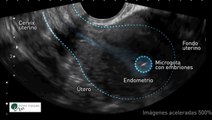

Ectogenesis: El utero artificial (Seleccion de embriones)

Ectogénesis de embriones y fetos requeriría un útero artificial. Un útero artificial tendría que ser suministrados por nutrientes y oxígeno de alguna fuente a innato un feto, así como disponer de material de desecho. Allí le gustaría ser una necesidad para una interfaz entre un proveedor, llenando esta función de la placenta. Un útero artificial, como un órgano de reemplazo, podría utilizarse para ayudar a las mujeres con útero dañada o enferma para aprovechar el feto concebirse a término. También tiene el potencial para mover el umbral de la viabilidad fetal a una etapa mucho más temprana del embarazo. Esto tendría implicaciones para la controversia actual con respecto a los derechos reproductivos humanas.